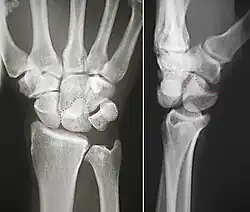

![]() Left hand anterior view (palmar view). Lunate bone shown in red. | |

The lunate bone (semilunar bone) is a carpal bone in the human hand. It is distinguished by its deep concavity and crescentic outline. It is situated in the center of the proximal row carpal bones, which lie between the ulna and radius and the hand. The lunate carpal bone is situated between the lateral scaphoid bone and medial triquetral bone.

The lunate is a crescent-shaped carpal bone found within the hand. The lunate is found within the proximal row of carpal bones. Proximally, it abuts the radius. Laterally, it articulates with the scaphoid bone, medially with the triquetral bone, and distally with the capitate bone. The lunate also articulates on its distal and medial surface with the hamate bone.[2]: 708 [3]